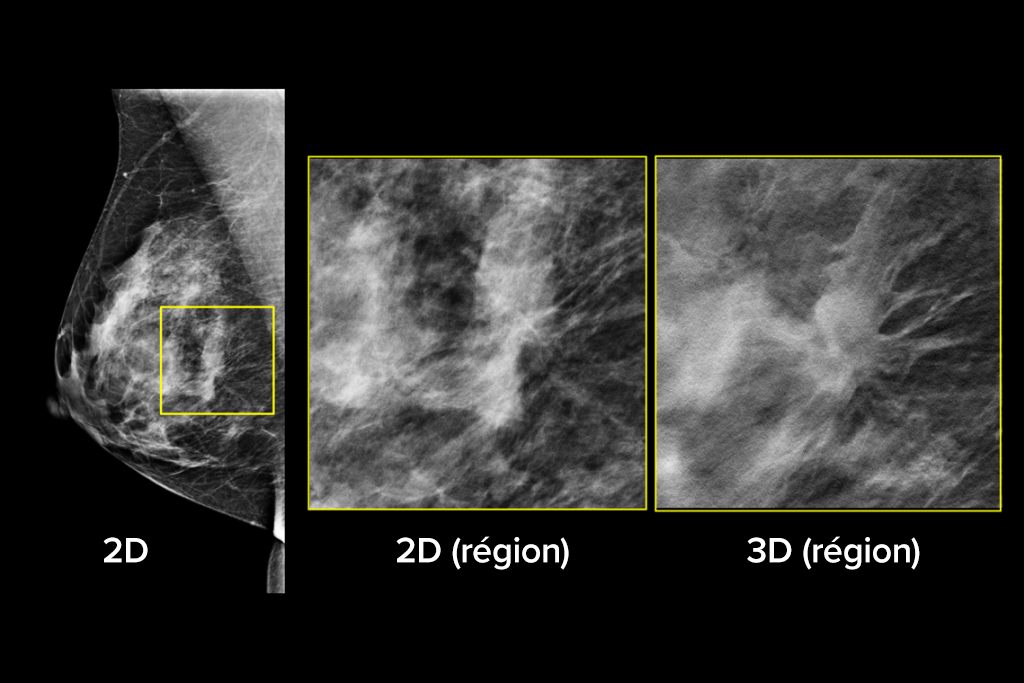

Le système Selenia Dimensions bénéficie de la précision prouvée de notre examen 3D Mammography pour détecter beaucoup plus tôt davantage de cancers invasifs du sein et diminuer les rappels par rapport à la 2D seule.2-6,*

Détectez jusqu’à 65 % de cancers invasifs en plus et réduisez les rappels de 40 % par rapport à la 2D seule.2-4,*

Une plus grande précision pour les femmes présentant des seins denses par rapport à la 2D seule.6